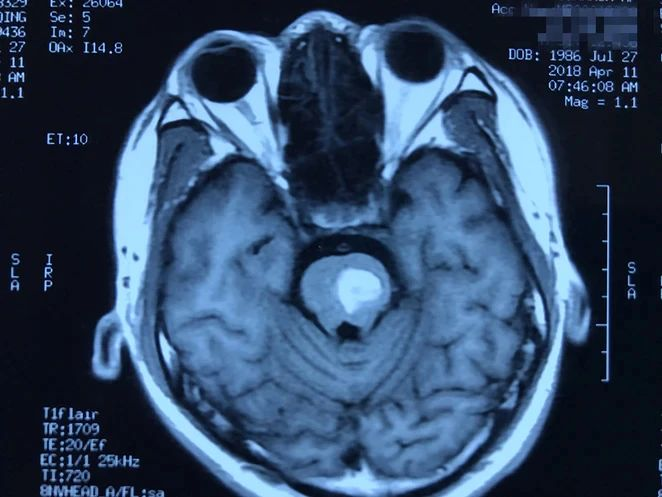

病人多发脑海绵状血管畸形,本次出血部位位于桥脑。第一次出血,术前偏瘫,转入我病房时为出血一月左右,采取颞下岩前入路切除脑干病变,术后病人肢体肌力较术前有提高,目前尚未出院。

本次手术资料: